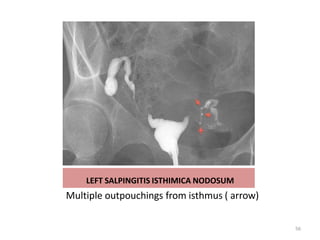

SALPINGITIS ISTHMICA NODOSA

(Diverticulosis of the fallopian tube)

• Irregular benign extensions of the tubal epithelium into the myosalpinx

mainly at the isthmic/proximal portion

• Out pouchings of isthmus

• Unilateral or bilateral

• Unknown cause

• Associated with infertility,

PID and ectopic pregnancy

LEFT SALPINGITIS ISTHIMICA NODOSUM

Multiple outpouchings from isthmus ( arrow)